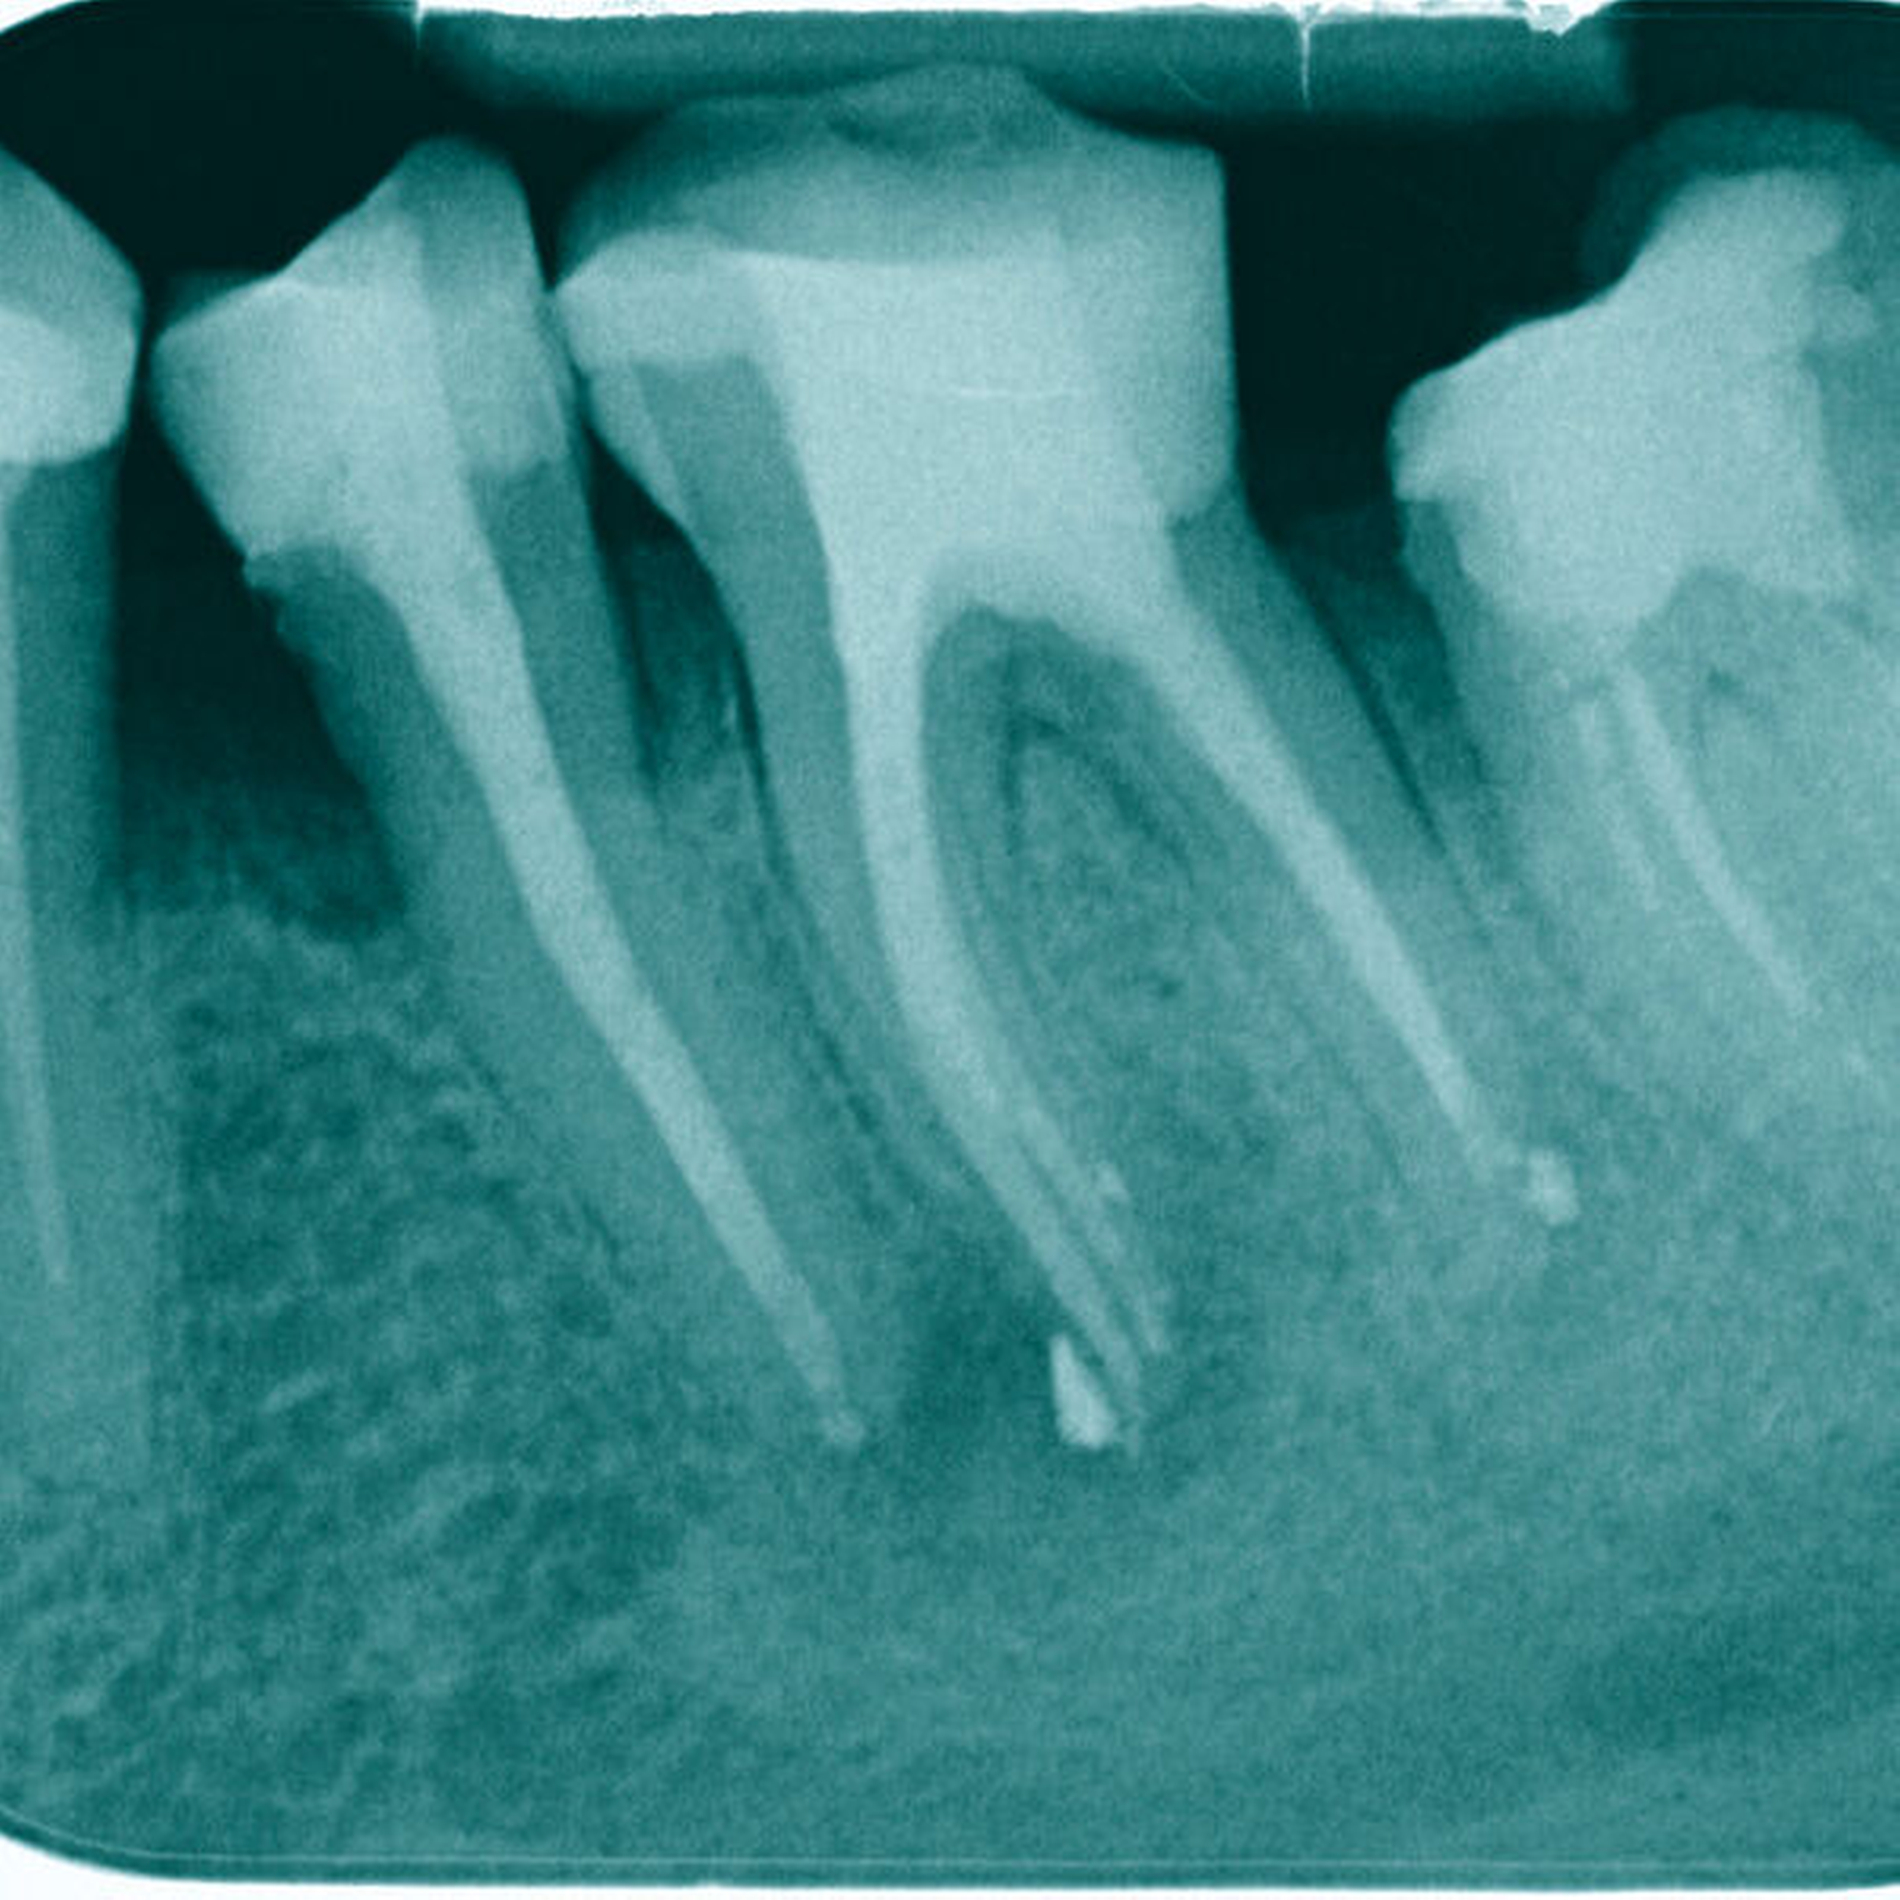

Das eingeschraubte Fragment wurde koronal mittels Ultraschalltechnik (VDW Ultra, VDW, München, Deutschland; Endo-Chuck, B&L Biotech, Fairfax, USA) 3 mm freigelegt und aufgerichtet. Anschließend konnte das Fragment mit der Tube-Dorn-Apparatur gegriffen und entfernt werden (Abbildung 4). Daraufhin wurde Durchgängigkeit in allen drei Wurzelkanälen erreicht und es erfolgte die chemomechanische Aufbereitung. In der nächsten Sitzung wurde die Obturation mit Guttapercha und AH Plus (Dentsply Sirona, York, USA) warm-vertikal modifiziert nach Schilder durchgeführt (Abbildung 5).